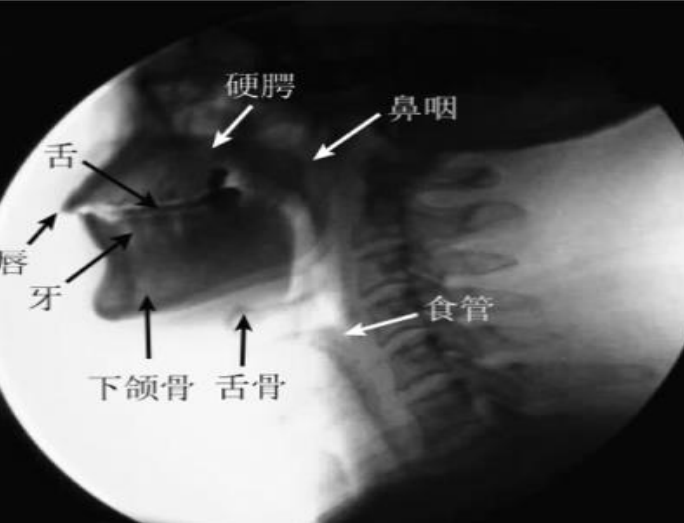

经过多年的努力与发展,目前我们医院拥有专业的吞咽治疗室及吞咽治疗师,能够完成吞咽相关评估及治疗,其中吞咽造影检查(VFSS)是检查吞咽功能最常用的方法,是吞咽障碍检查和诊断的“金标准”,我科与我院影像科合作开展,其在X线透视下,针对口、咽、喉、食管的吞咽运动所进行的特殊造影,其可视化特点有利于观察吞咽过程各个时期的特点,主要包括:

(1)口腔期

(2)咽期、食管期